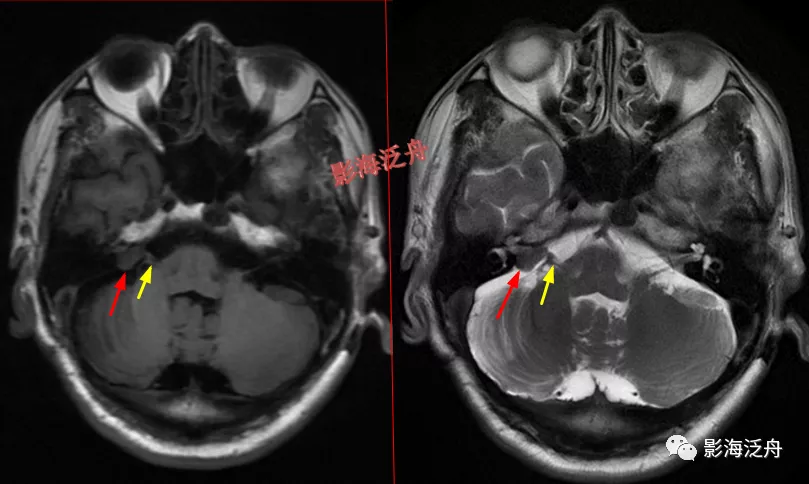

脑膜炎患者,桥前池内可见异常增多的血管影(红箭),正常人的桥前池因为脑脊液流动产生的伪影也可以看到池内絮状低信号(绿箭),但不如右侧患者的明显,这个观察起来比较困难,就如在腹部CT上观察患者是否存在肝脏肿大一样,需要一个经验积累的过程。黄箭指基底动脉,蓝箭指三叉神经。